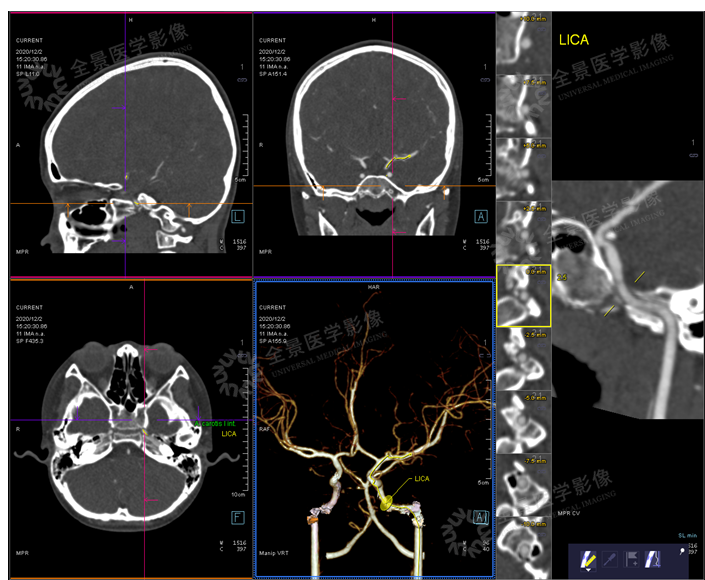

右侧额叶、基底节与对侧比较,CBF下降明显,CBV无明显差异,

MTT、TTD时间明显延长。(前循环供血范围)

CTA示:右侧颈内动脉闭塞,颅内血管多发粥样硬化。

CTV示:静脉未见明显异常。

右侧颞叶与左侧比较,CBF稍增加,CBV无明显差异,MTT、TTD时间稍延长。

通过多期的血管重建,发现右侧颞叶附近有明显的侧枝循环建立。